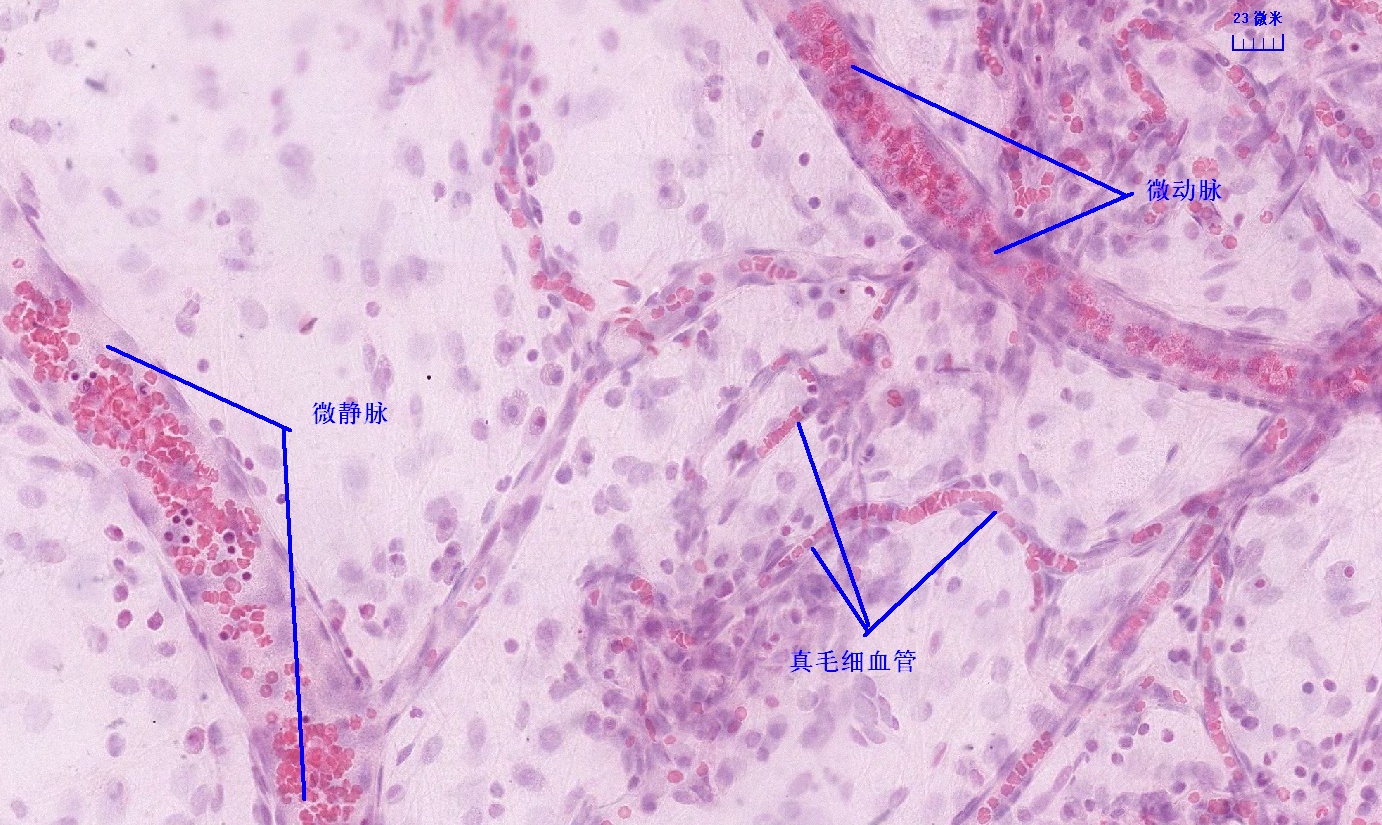

6 第六单元 循环系统

6.1 循环系统切片库

6.2 循环系统微课

6.3 循环系统课件